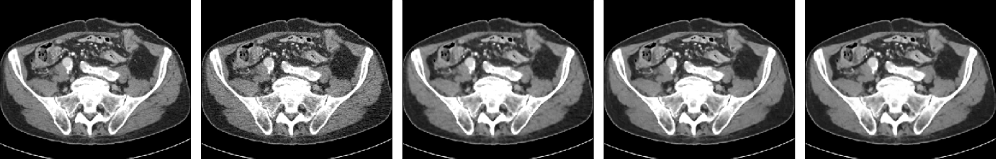

We show two source images and three restored images in Figs. 2(a)-(e) for visual comparison in global and local views. GUSL and CTformer stand out among the three benchmarks. GUSL can productively restore the LDCT images against image noise while effectively preserving the global structures and the local details of images.